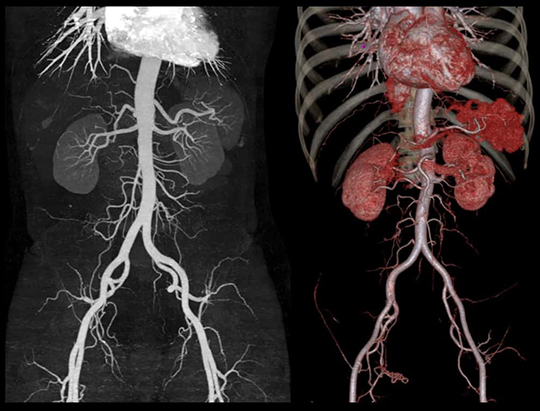

This fully configured 80-slice diagnostic CT produces high image quality with low radiation dose that can be used as a standalone or back-up CT for Radiology procedures.